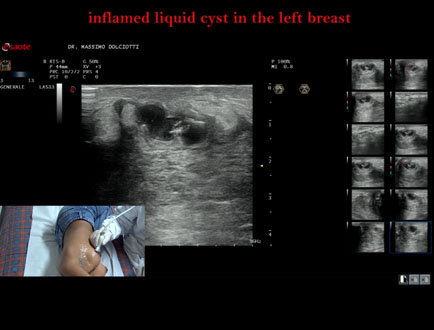

Data inserimento: 07/10/2025

Ecografia del: 15/05/2025

Strumento: Esaote MyLab Eight

Sonda: Lineare Multifrequenza 3-13 MHz

Età Paziente: F 16 anni

Motivazione dell'esame: da 2 giorni dolore alla mammella sinistra.

Commento all'esame: le immagini ed il video documentano al quadrante inferiore esterno ore 4 della mammella sinistra, formazione disomogenea ipoanecogena, delle dimensioni di 24 x 14 mm, da ricondurre a cisti liquida infiammata.

Conclusioni: cisti liquida flogosata alla mammella sinistra (inflamed liquid cyst in the left breast).

Presentazione: Dr. Massimo Dolciotti - Ancona